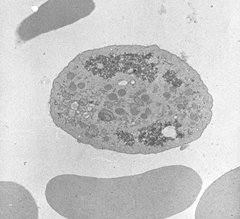

A constant characteristic is the presence of a small number of noticeably large platelets with a fairly rounded shape (macrothrombocytopenia). Laboratory tests typically include platelet counts as well as analysis of blood smears (Lanza, 2006).

ImageI

Electron Micrograph - BSS Giant Platelet;

Image provided by Mathieu Fiore, Hôpital Xavier Arnozan, Pessac, Franc